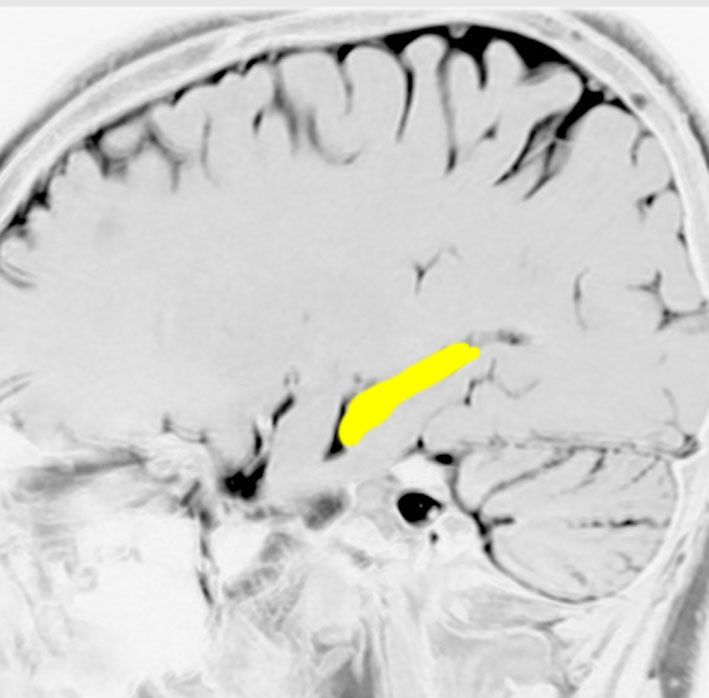

左の海馬を横から見たところです

記憶の中枢であり,この部位の機能低下は認知症を招きます

アルツハイマー病の原因ともなる部位です